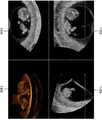

도 11은 본 개시의 일부 실시예에 따른, 초음파 진단 장치(1000)가 2 차원 초음파 영상 내의 영역 중 3 차원 초음파 영상으로 렌더링되지 않은 영역을 2 차원 초음파 영상 상에 디스플레이하는 예시를 나타내는 도면이다.FIG. 11 is a diagram illustrating an example of displaying an area of the 2-dimensional ultrasound image, which is not rendered as a 3-dimensional ultrasound image, on the 2-dimensional ultrasound image, according to some embodiments of the present disclosure.

도 11을 참조하면, 초음파 진단 장치(1000)는 2 차원 초음파 영상 내의 영역 중 3 차원 초음파 영상(1108)으로 렌더링되지 않은 영역(1110)을 2 차원 초음파 영상 상에 디스플레이할 수 있다.Referring to FIG. 11, the ultrasound

초음파 진단 장치(1000)는 A 단면 영상(1102) 상에 관심 영역(110)을 설정하는 사용자 입력을 수신할 수 있다. 관심 영역(110)을 설정하는 사용자 입력을 수신함에 따라, 초음파 진단 장치(1000)는 설정된 관심 영역(110)에 대한 3 차원 볼륨을 생성할 수 있다. 또한, 초음파 진단 장치(1000)는 결정된 3 차원 볼륨을 렌더링함으로써 3 차원 초음파 영상을 생성하고, 생성된 3 차원 초음파 영상을 디스플레이할 수 있다.The ultrasound

사용자가 자궁 내막 아래의 자궁 용종에 대한 3 차원 초음파 영상을 보고자 할 경우, 사용자가 설정한 관심 영역은 자궁 용종 뿐만 아니라 자궁 용종과 붙어있는 자궁 내막을 포함할 수 있다. 관심 영역의 시작 지점이 자궁 내막에 위치함에 따라, 초음파 진단 장치(1000)는 자궁 내막을 디스플레이 볼륨의 표면으로 하는 3 차원 초음파 영상을 디스플레이할 수 있다. 초음파 진단 장치(1000)는 3 차원 초음파 영상 내의 자궁 내막 영역을 깎는 사용자 입력을 수신함에 따라, 자궁 용종을 표면으로 하는 3 차원 초음파 영상(1108)을 디스플레이할 수 있다.When a user wishes to view a 3-dimensional ultrasound image of the uterine polyp under the endometrium, the region of interest set by the user may include the uterine polyp as well as the endometrium attached to the uterine polyp. As the starting point of the region of interest is located in the endometrium, the ultrasound

초음파 진단 장치(1000)는 A 단면 영상(1102) 상에 3 차원 초음파 영상(1108)으로 렌더링 되지 않은 영역(1110)을 디스플레이할 수 있다.The ultrasound

예를 들어, 초음파 진단 장치(1000)는 A 단면 영상(1102) 내의 영역 중 렌더링이 시작된 지점들을 결정하고, 결정된 지점들을 잇는 선(1120)을 A 단면 영상(1102) 상에 디스플레이할 수 있다. 렌더링이 시작된 지점들을 잇는 선(1120)은 3 차원 초음파 영상(1108)으로 표현된 디스플레이 볼륨의 표면의 위치를 나타내는 선을 의미할 수 있다.For example, the ultrasound

초음파 진단 장치(1000)는 렌더링이 시작된 지점들을 잇는 선(1120)을 기준으로, A 단면 영상(1102) 내의 영역 중 렌더링 방향의 반대 방향의 영역을 렌더링되지 않은 영역(1110)으로 결정할 수 있다. 또한, 초음파 진단 장치(1000)는 렌더링되지 않은 영역(1110)을 다른 영역과 구분하여 디스플레이할 수 있다. 예를 들어, 초음파 진단 장치(1000)는 렌더링되지 않은 영역(1110)을 2 차원 초음파 영상 내의 다른 영역과 구분될 수 있는 색으로 디스플레이함으로써 렌더링되지 않은 영역(1110)을 표시할 수 있다. 이 경우, 초음파 진단 장치(1000)는 렌더링되지 않은 영역(1110)상에 2 차원 초음파 이미지 영역이 비치도록 투명하게 색을 디스플레이함으로써 렌더링되지 않은 영역임을 나타냄과 동시에 B 모드 이미지로 표현된 구조물의 형태를 나타낼 수 있다.The ultrasound

또한, 초음파 진단 장치(1000)는 B 단면 영상(1104) 상에 3 차원 초음파 영상(1108)으로 렌더링 되지 않은 영역(1110)을 디스플레이할 수 있다. 또한, 초음파 진단 장치(1000)는 C 단면 영상(1106) 상에 3 차원 초음파 영상(1108)으로 렌더링 되지 않은 영역(1110)을 디스플레이할 수 있다.In addition, the ultrasound

이에 따라, 사용자는 자신이 설정한 관심 영역(110) 중 3 차원 초음파 영상으로 렌더링된 영역과 렌더링되지 않은 영역(1110)을 확인할 수 있다.

도 12는 본 개시의 다른 일부 실시예에 따른, 초음파 진단 장치(1000)가 2 차원 초음파 영상 내의 영역 중 3 차원 초음파 영상으로 렌더링되지 않은 영역을 2 차원 초음파 영상 상에 디스플레이하는 예시를 나타내는 도면이다.12 is a diagram illustrating an example in which an ultrasonic

도 12를 참조하면, 디스플레이 볼륨의 표면의 깊이를 조절하는 사용자 입력을 수신함에 따라, 초음파 진단 장치(1000)는 2 차원 초음파 영상 내의 영역 중 3 차원 초음파 영상(1108)으로 렌더링되지 않은 영역(1110)을 2 차원 초음파 영상(40) 상에 디스플레이할 수 있다.12, the ultrasound

도 12를 참조하면, 도 12에 도시된 2 차원 초음파 영상(40)은 도 5에 도시된 2 차원 초음파 영상이며, 도 12에 도시된 3 차원 초음파 영상들(52, 54, 56)은 도 5에 도시된 3 차원 초음파 영상(50)에서, 태아의 손(536) 영역이 깎아지는 정도에 따라, 디스플레이 볼륨의 표면의 깊이가 변경된 영상들이다.12, the two-

도 12(a)는 태아(534)의 손(536)이 덜 제거된 경우를 나타내며, 도 12(b)는 태아(534)의 손(536)뿐만 아니라 태아(534)의 손(536)이 가리고 있던 태아(534)의 눈까지 제거된 경우를 나타내며, 도 12(c)는 태아(534)의 손(536)이 적당히 제거된 경우를 나타낸다.12 (a) shows a case where the

도 5에 도시된 3 차원 초음파 영상(50) 내의 디스플레이 볼륨의 깊이가 변경됨에 따라, 초음파 진단 장치(1000)는, 2 차원 초음파 영상(40) 상에 3 차원 초음파 영상(52, 54, 56)으로 렌더링되지 않은 영역을 디스플레이할 수 있다. 도 12에 도시된 바와 같이, 태아(534)의 손(536)이 제거되는 깊이가 깊어질수록, 2 차원 초음파 영상(40)에 표현된 렌더링되지 않은 영역이 아래로 더 확장됨을 알 수 있다.The depth of the display volume in the

도 12에 도시된 2 차원 초음파 영상(40)에 디스플레이된, 렌더링되지 않은 영역을 비교하면, 태아(534)의 손(536)이 적당히 제거된 도 12(c)에 표시된 영역(1230)은, 태아(534)의 손(536)이 덜 제거된 도 12(a)에 표신된 영역(1210)보다 아래로 더 확장되어 있음을 알 수 있다. 또한, 태아(534)의 눈까지 제거된 도 12(b)에 표시된 영역(1220)은 태아(534)의 손(536)이 적당히 제거된 도 12(c)에 표시된 영역(1230) 보다 아래로 더 확장되어 있음을 알 수 있다.When comparing the un-rendered areas displayed on the two-

사용자는 2 차원 초음파 영상(40) 상에 디스플레이된 3 차원 초음파 영상(52, 54, 56)으로 렌더링되지 않은 영역을 확인함으로써, 디스플레이 볼륨 중 일부를 삭제하거나 되살릴 수 있다.

도 14a 및 14b는 본 개시의 다른 일부 실시예에 따른, 초음파 진단 장치(1000)가 2 차원 초음파 영상 내의 영역 중 3 차원 초음파 영상으로 렌더링되지 않은 영역을 2 차원 초음파 영상 상에 디스플레이하는 예시를 나타내는 도면이다.14A and 14B illustrate an example in which an ultrasound

도 14a를 참조하면, 초음파 진단 장치(1000)는 자궁 내의 태아의 서로 다른 단면을 나타내는 2 차원 초음파 영상(1402 내지 1406) 및 2 차원 초음파 영상(1402) 상에 설정된 관심 영역에 대한 3 차원 초음파 영상(1408)을 디스플레이할 수 있다.14A, the ultrasound

이 경우, 초음파 진단 장치(1000)는 도 5에 도시된 바와 같이 디스플레이 볼륨의 표면을 나타내는 3 차원 초음파 영상이 아닌, 디스플레이 볼륨의 윤곽선만을 나타내고, 디스플레이 볼륨의 내부는 투명 또는 반투명하게 나타내는 3 차원 초음파 영상(1408)을 디스플레이할 수 있다. 예를 들어, 초음파 진단 장치(1000)는 태아의 윤곽선만을 나타내고, 태아 내부는 투명 또는 반투명하게 나타내는 3 차원 초음파 영상(1408)을 디스플레이할 수 있다.In this case, the ultrasound

도 14b를 참조하면, 초음파 진단 장치(1000)는 2 차원 초음파 영상(1402 내지 1406) 내의 영역 중 3 차원 초음파 영상(1408)으로 렌더링되지 않은 영역을 2 차원 초음파 영상(1402 내지 1406) 상에 디스플레이할 수 있다.14B, the ultrasound

3 차원 초음파 영상(1408)이 디스플레이 볼륨 내의 구조물의 윤곽선만을 나타내는 경우, 초음파 진단 장치(1000)는 2 차원 초음파 영상(1402 내지 1406) 내의 태아의 피부의 윤곽선(1410)만을 렌더링된 영역으로 나타내고, 태아의 내부 영역(1420)을 렌더링되지 않은 영역으로 나타낼 수 있다.